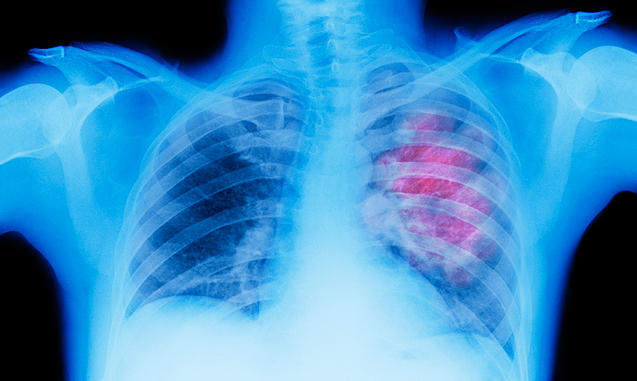

Στο Κέντρο Μοριακής Ανοσολογίας (CIM) στην Κούβα διατίθεται δωρεάν, το πρώτο εμβόλιο στους ασθενείς με καρκίνο του πνεύμονα. Σύμφωνα με τους ειδικούς είναι μια νέα θεραπεία, μοναδική στον κόσμο, η οποία μπορεί να σταματήσει την εξέλιξη της νόσου, χωρίς να επηρεάζει την ποιότητα ζωής των ανθρώπων.

«Τα αποτελέσματα του εμβολίου δίνουν ένα ποσοστό επιβίωσης των ασθενών, ο όγκος δεν εξαλείφεται, αλλά σταματά να αναπτύσσεται, επιτρέποντας στους ασθενείς να ζουν περισσότερο και ιδιαίτερα με μια καλή ποιότητα ζωής, οι παρενέργειες είναι ελάχιστες», λέει η γιατρός Arlhee Diaz.